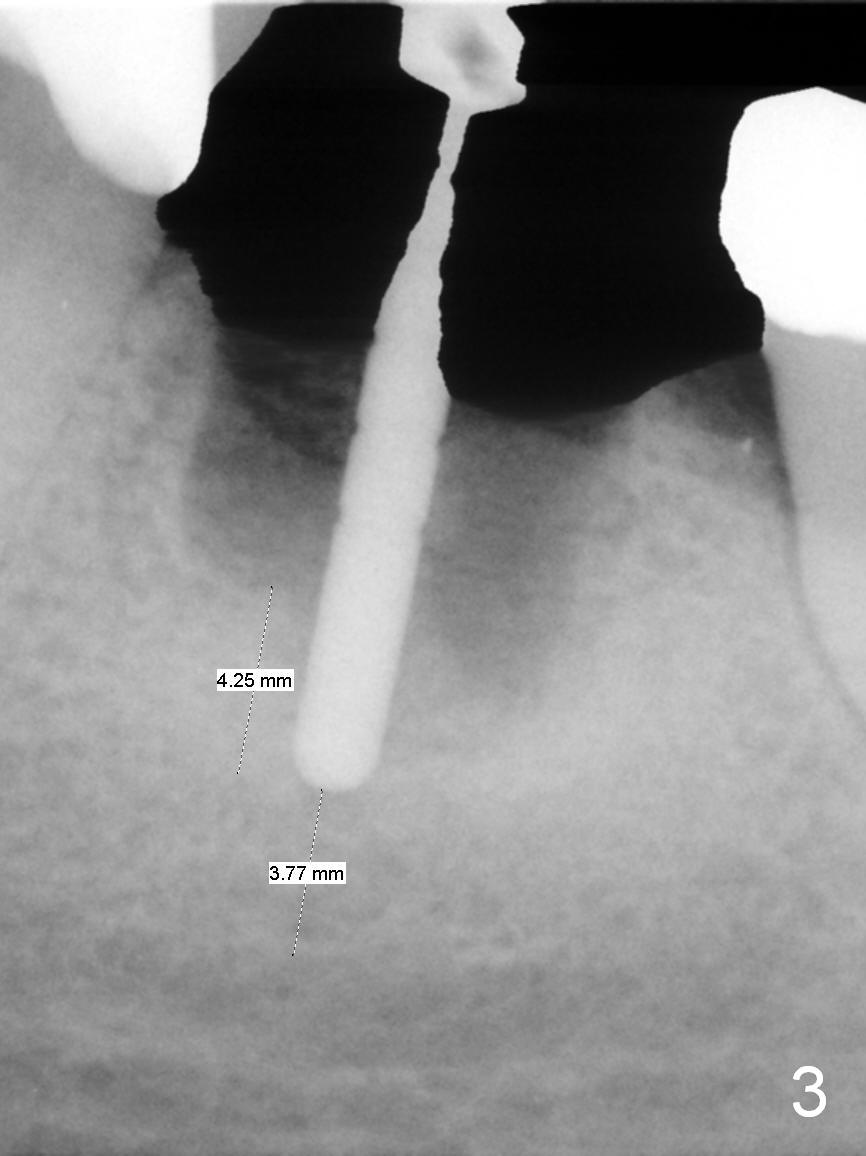

A 56-year-old lady (YW) has diabetes II, fairly well controlled. Although there is radiologic evidence of mesial root fracture of the tooth #19 (Fig.1 (panoramus)), she is asymptomatic. The buccal gingiva is slightly erythematous and edematous. There is no deep pocket. According to Fig.1, either the buccal or lingual wall is lost. This is not evident from Fig.2 (PA). Osteotomy is established in the septum or the distal socket (treated with Clindamycin), away from the lost plate (Fig.6,7). It is estimated that there is 4-5 mm apical bone. Measure the depth of the socket. Osteotomy should be 3 mm beyond the socket.

In fact, the buccal plate and the septum are defective. Osteotomy is initiated lingual to the center of the common sockets (Fig.1); depth is about 4 mm. When a 5x12 mm bone-level implant is placed (Fig.4), there is a gap mesiobuccally, which is later filled with bone graft (Fig.5 *). A large abutment (7.8x4(3) mm) is placed immediately (Fig.5 A) for an immediate provisional to close the sockets. The buccal abutment margin is ~ 1 mm subgingival, whereas the lingual ~2 mm supragingival. The abutment may need to be changed in the restorative phase (Fig.9,10).